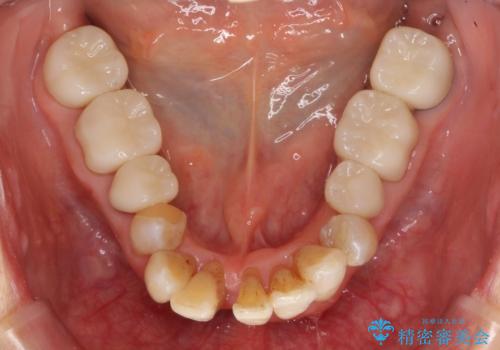

銀歯を高強度の仮歯に替えたのち、下顎前歯のみの部分矯正→全体的なマウスピース矯正治療(インビザライン)→最終的なセラミック治療と治療を進めます。

矯正治療と目立つ銀歯のやりかえを行ったことでかみあわせだけでなく、審美性・清掃性も改善し口腔内の環境を劇的に改善することができました。